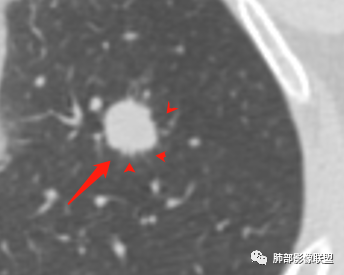

病例1为胸膜下实性小结节,血管脐凹样出入,可见支气管阻塞。病灶膨隆,部分边缘平直,周围晕征不明显,未见分叶,但可见毛刺及胸膜牵拉,增强后明显强化,老年男性,怀疑新生物尤其是腺癌是有理由的。

胸膜下结节,边界清楚、光滑,边缘稍凹陷,有胸膜牵拉

除了胸膜牵拉,还有短毛刺?血管纠集

似乎有脐凹征

支气管在门口堵塞